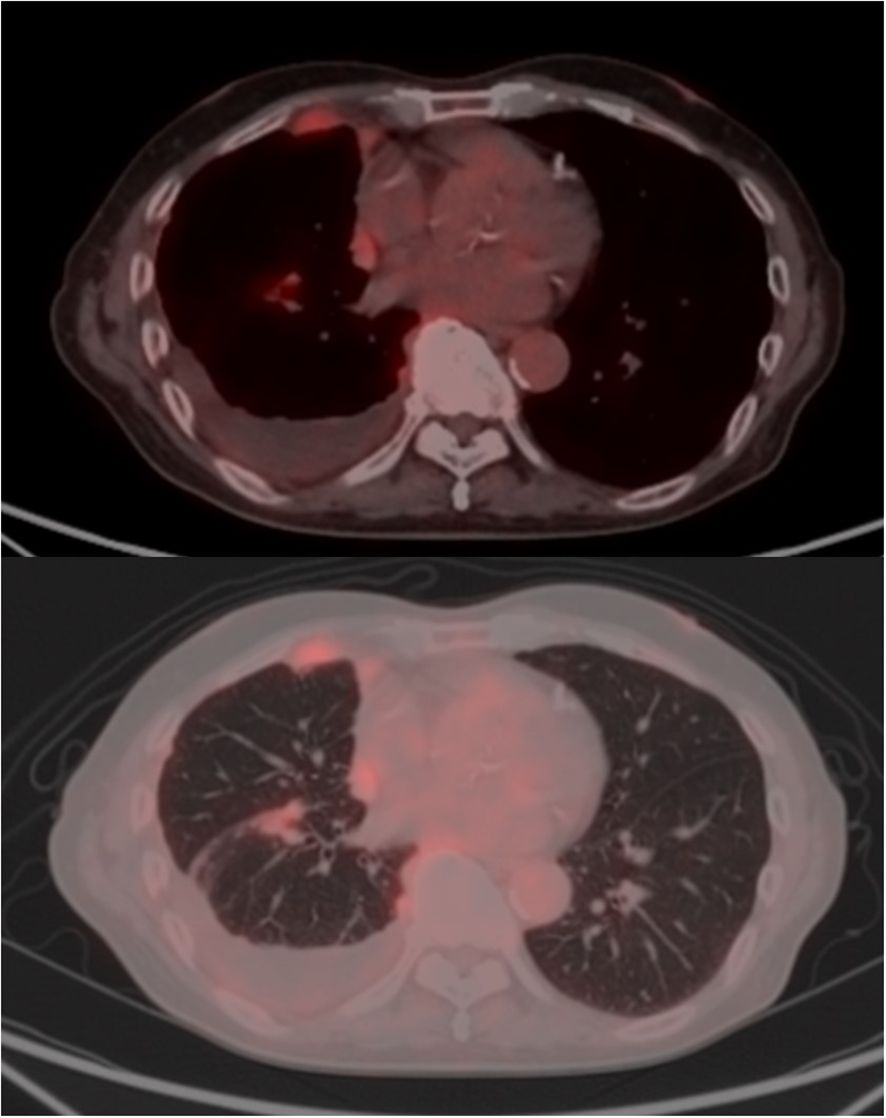

Tocilizumab was reintroduced, after which no new immune-related adverse events were observed. The patient showed a remarkable response to just a single cycle of immunotherapy. His pleural effusion resolved completely, and the solid mesothelioma lesions also showed a durable reduction (Figure 3). As a result, he no longer required any pleural drainage that was necessary before treatment. The patient’s clinical condition remained stable, with no recurrence of pleural effusion or neurological symptoms until day 250. The overall clinical course of the patient, including therapies, adverse events, and key biomarker trends, is summarized in Figure 2.

Figure 3. Radiographic response to a single cycle of immunotherapy. CT scans after one cycle of nivolumab and ipilimumab, demonstrating a significant reduction in the solid tumor lesions (white arrows) and complete resolution of the pleural effusion. CRP, C-reactive protein; CRS, cytokine release syndrome; ICI, immune checkpoint inhibitor; IL-6, interleukin-6; irAE, immune-related adverse event; mPSL, methylprednisolone; PSL, prednisolone.